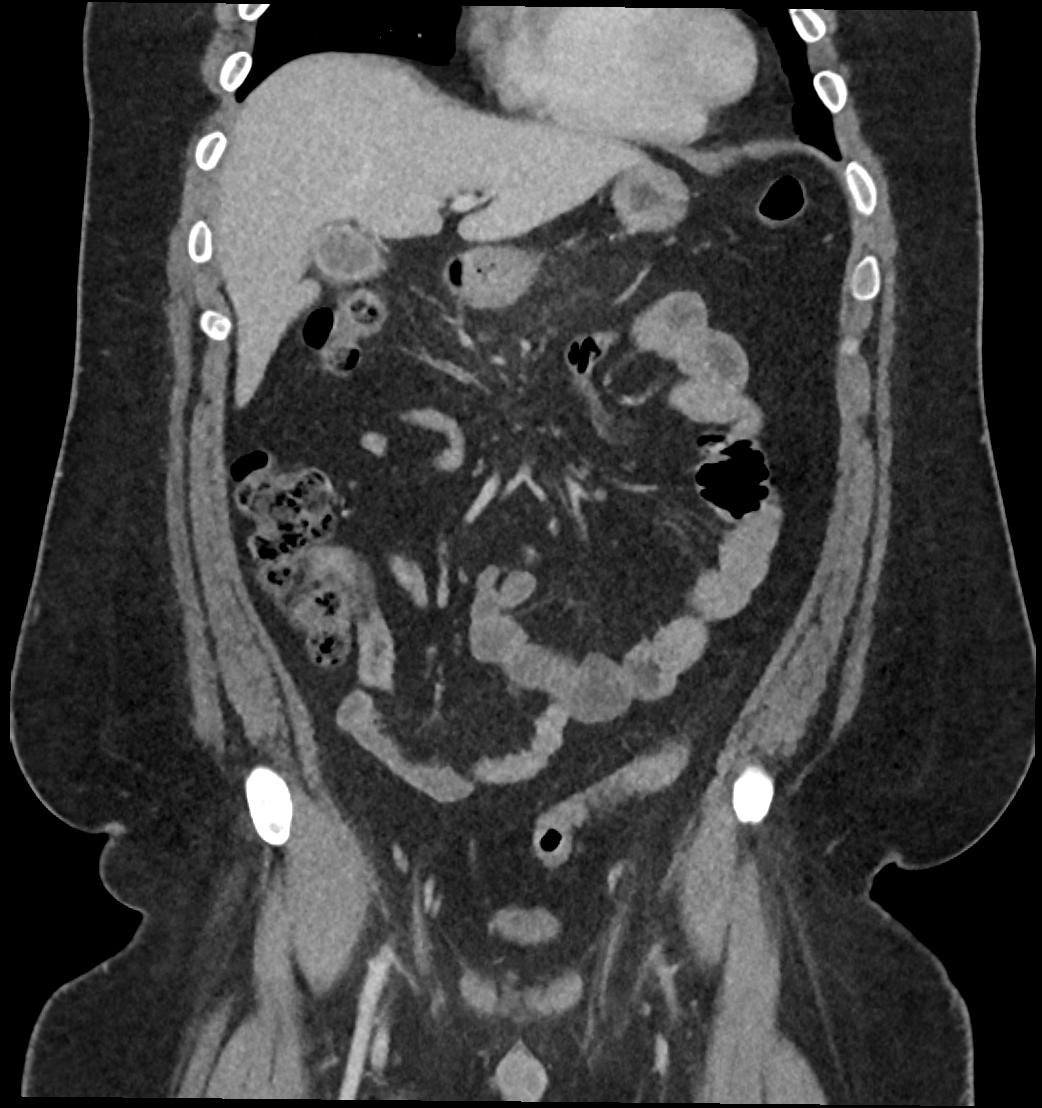

Patient: Padmakumar A. , *1988-04-24, PID: 3000069741773230809

Study Description: CT ABDOMEN

Image Series: Abdomen Cor 3mm [4]

<< Previous | Image 46 of 119 | Next >>